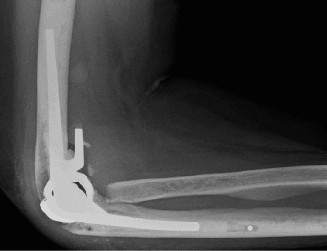

She has received multiple corticosteroid injections into her elbows over the past 3 years, but she no longer gets relief. Her images are shown (Figs. 2–99 to 2–102).

Figure 2–99

Figure 2–100

Figure 2–101

Figure 2–102

Approximately what percentage of patients with rheumatoid arthritis develop elbow involvement within 5 years?

The correct answer is (E). Between 20% and 50% of patients with rheumatoid arthritis will develop elbow arthritis. Isolated presentation of the elbow is rare and only occurs about 5% of the time. Care should be given to provide the best treatment for the entire upper extremity when evaluating and treating a patient with rheumatoid arthritis.

Which of the following is the procedure of choice when treating an advanced, debilitating rheumatoid elbow?

Discussion

The correct answer is (E). Semi-constrained total elbow is the definitive procedure of choice when treating an elbow with extensive articular damage and subluxation or ankylosis of the joint (see Fig. 2–103). Rheumatoid patients place a lower demand on the prosthesis than patients with primary osteoarthritis (OA), and thus have a lower incidence of mechanical loosening. Due to the ligamentous laxity, prosthetic instability is the complication that most commonly inhibits success.